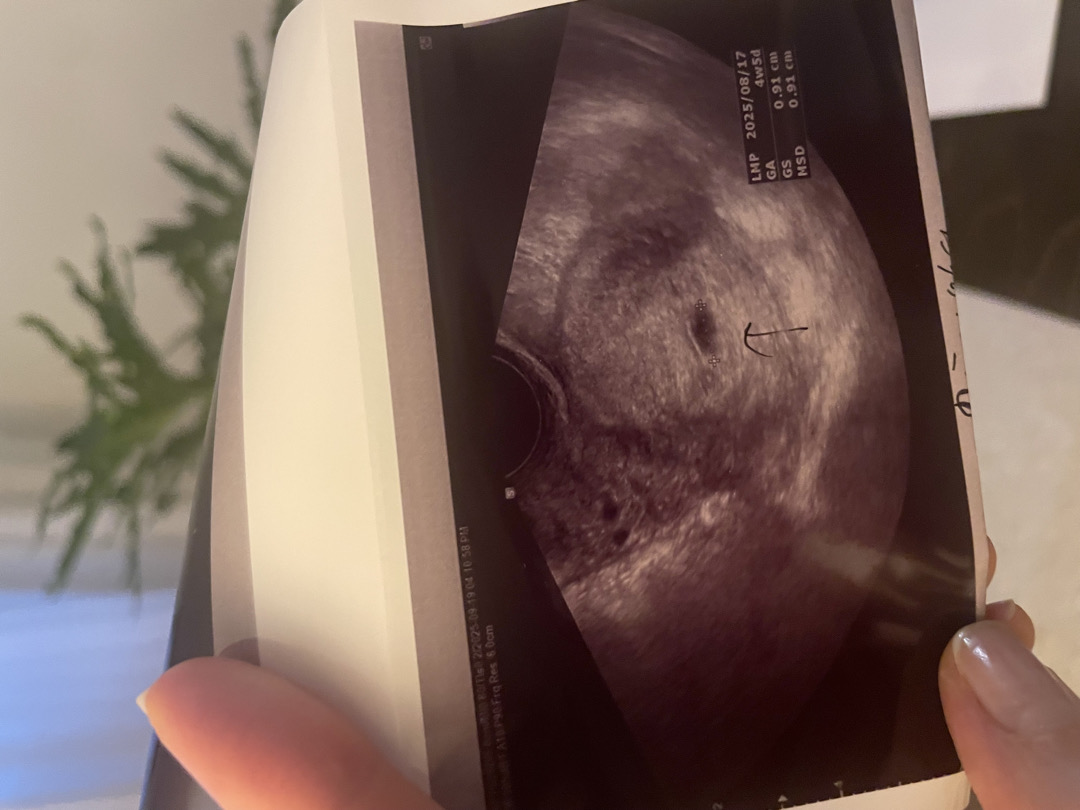

4주5일 아기집 0.91cm 보고오는길이에요🥹 1-2주 후에 다시 초음파 보러오라는데 그 때는 분만 병원을 정해서 가고싶어서요! 오늘 아기집 보고 온 곳은 집에서 가깝고 원장님이 다큐에 나오셔서 소신있게 진료보시는걸로 유명하더라고요 과잉진료도 없고요,, 마포쪽에 ㅈㅇㅂ 산부인과예요 근데 무통주사 없는 자연주의출산을 하는 곳이고 모자동실 하는 병원이니 잘 생각해보고 결정하라고 해서 고민이 많아졌어요 ㅜ 첫 출산이라 비교할 것도 없고 장단이 있겠지만 어떤걸 추천하시는지 ,,잘 모르겠어서 글 올려봅니다! 🧐 여러분은 어떤 선택을 추천하시나요?!